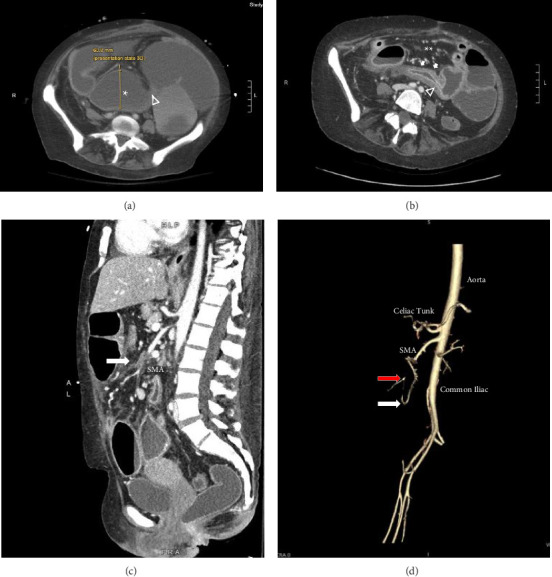

Small bowel strictures are a common complication of Crohn's disease (CD), which can lead to obstruction, perforation, and fistula formation. However, strictures can stem from other etiologies in CD patients, including malignancy, prior surgery, radiation, and ischemia. We present a patient who developed a new long-segment jejunal and ileal stricture within 2 months after ileocolic resection. What was initially treated as worsening CD was ultimately an unrelated ischemic stricture due to suspected superior mesenteric artery thrombosis following ileocolic resection. The contrasting location of the stricture compared to her previous disease, timing of progression, and lack of response to anti-inflammatory treatment prompted a reassessment of the underlying disease process.